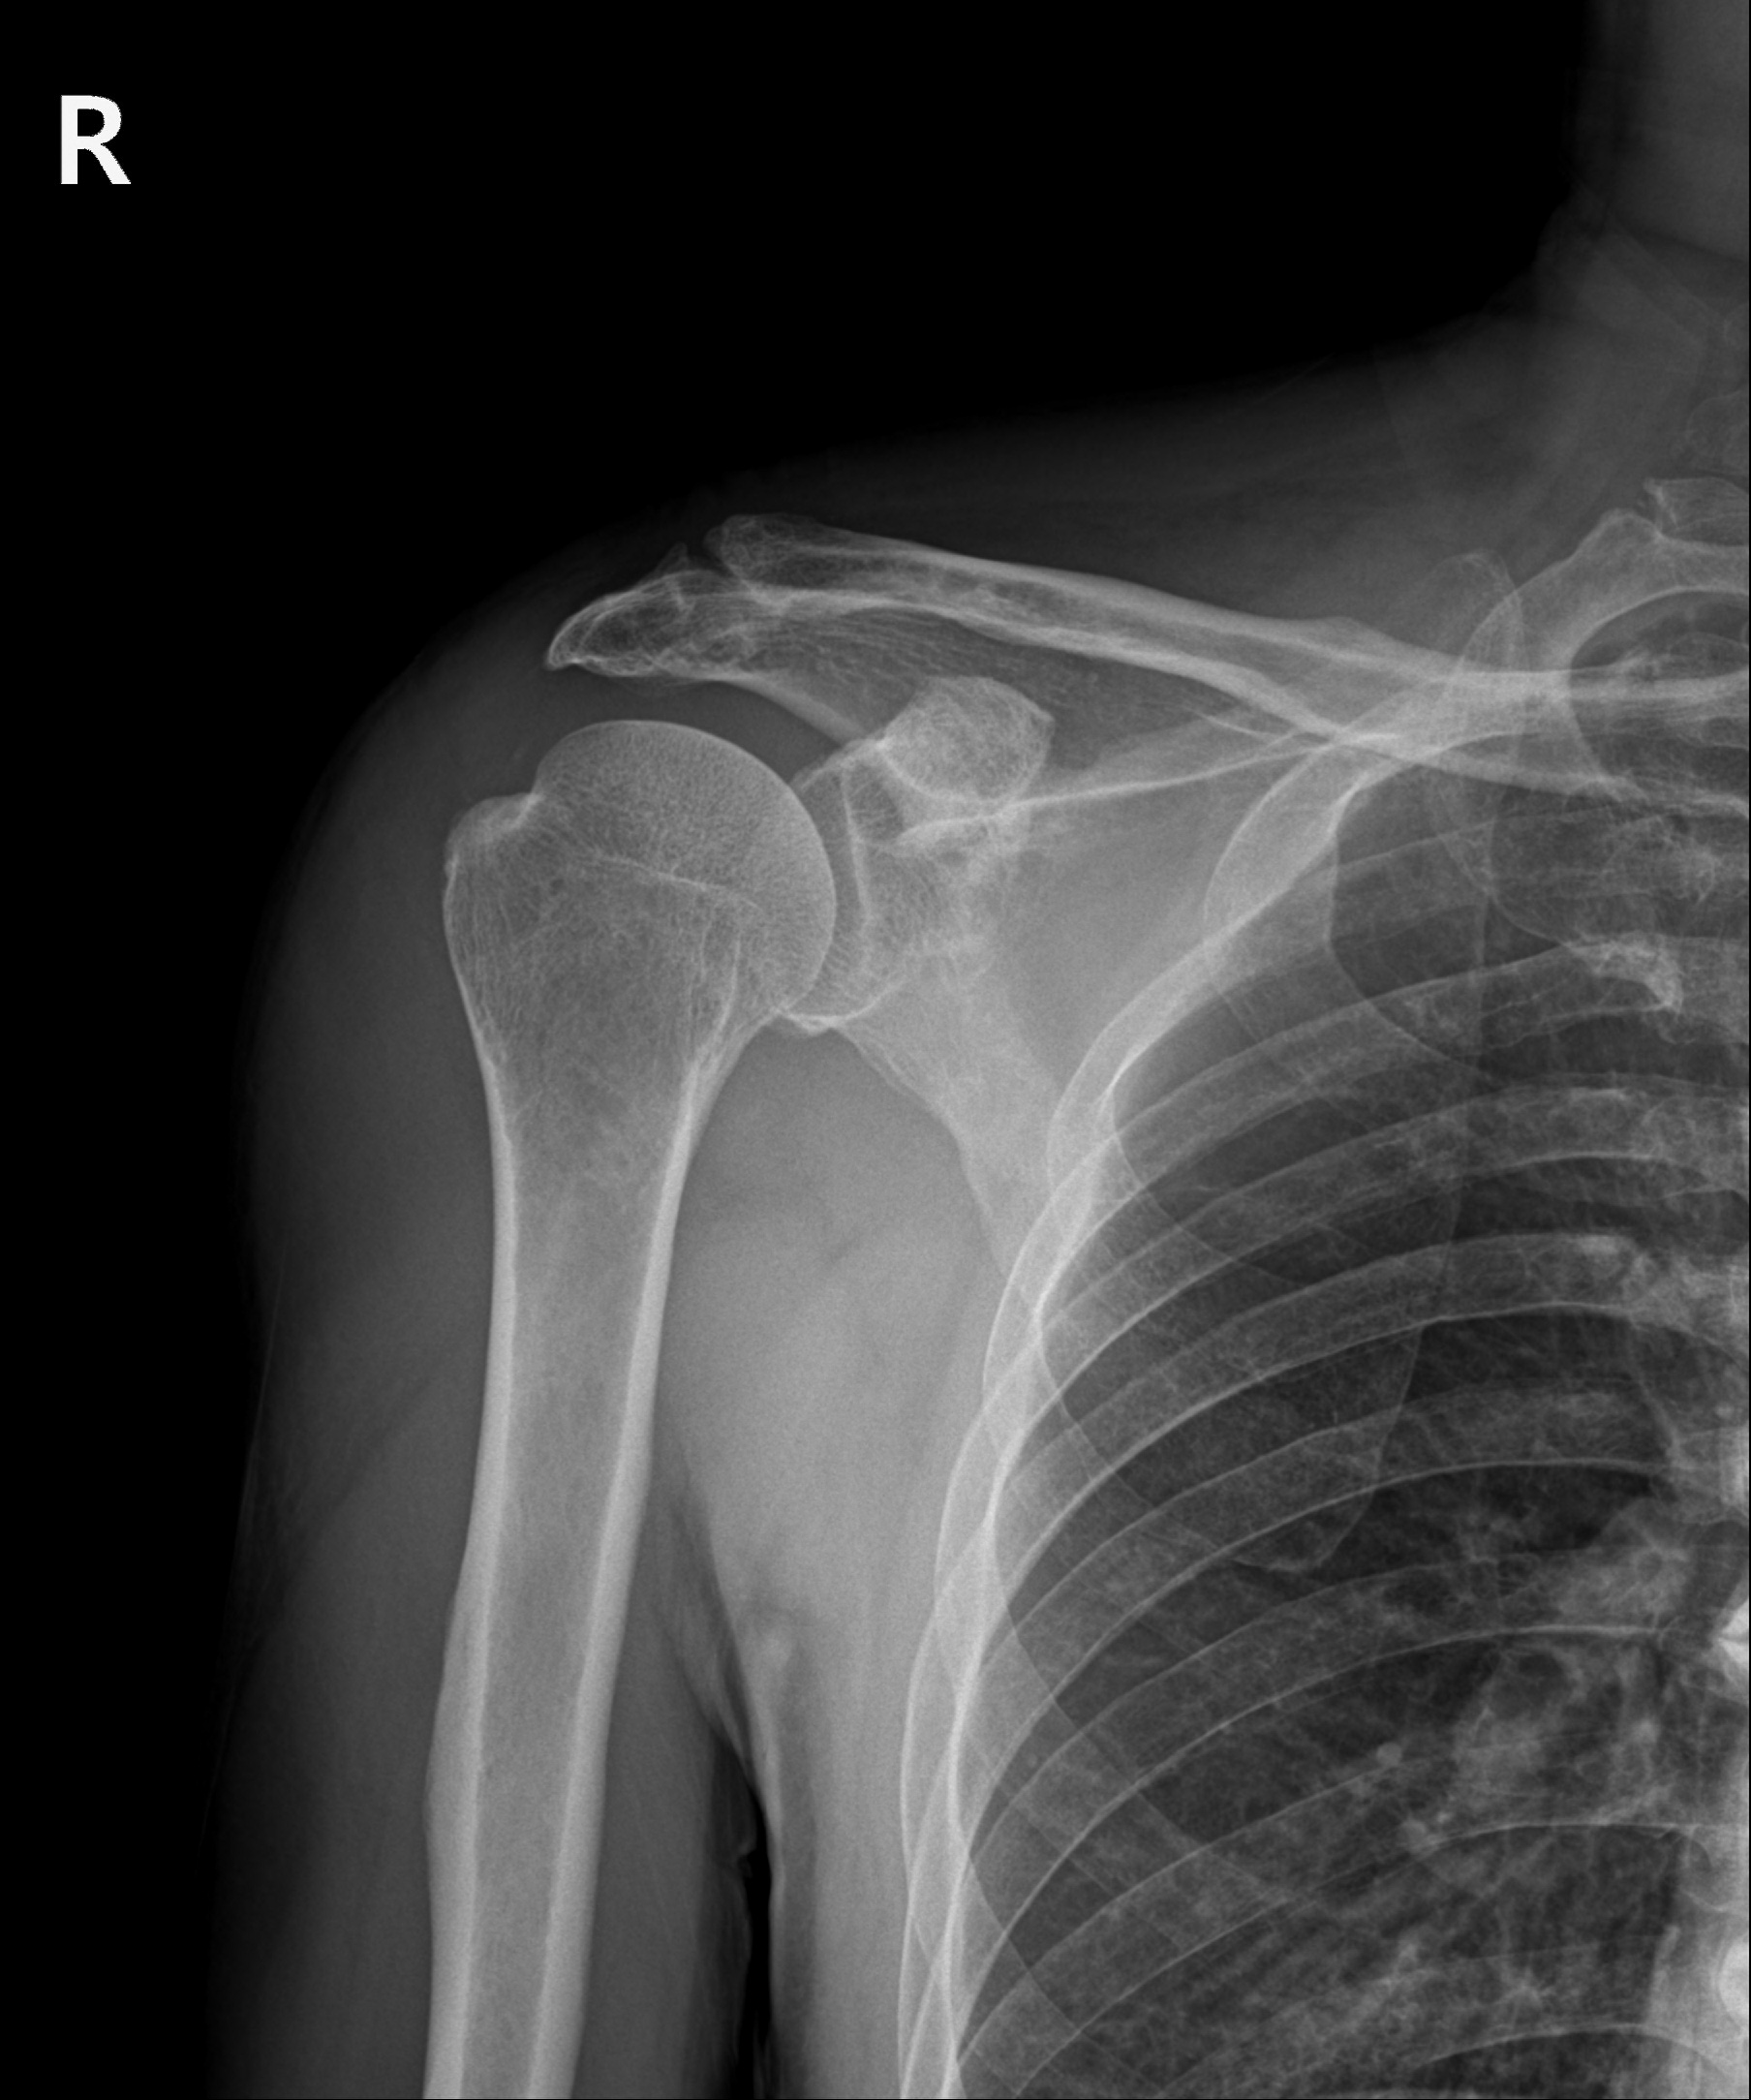

관절내시경을 통해 쇄골 끝부분을 절단해 제거한 모습

수술 X-ray

수술 후 X-ray

ㆍX-ray 전, 후 사진입니다 (전 : 2023.03.22 / 후 : 2023.03.29)